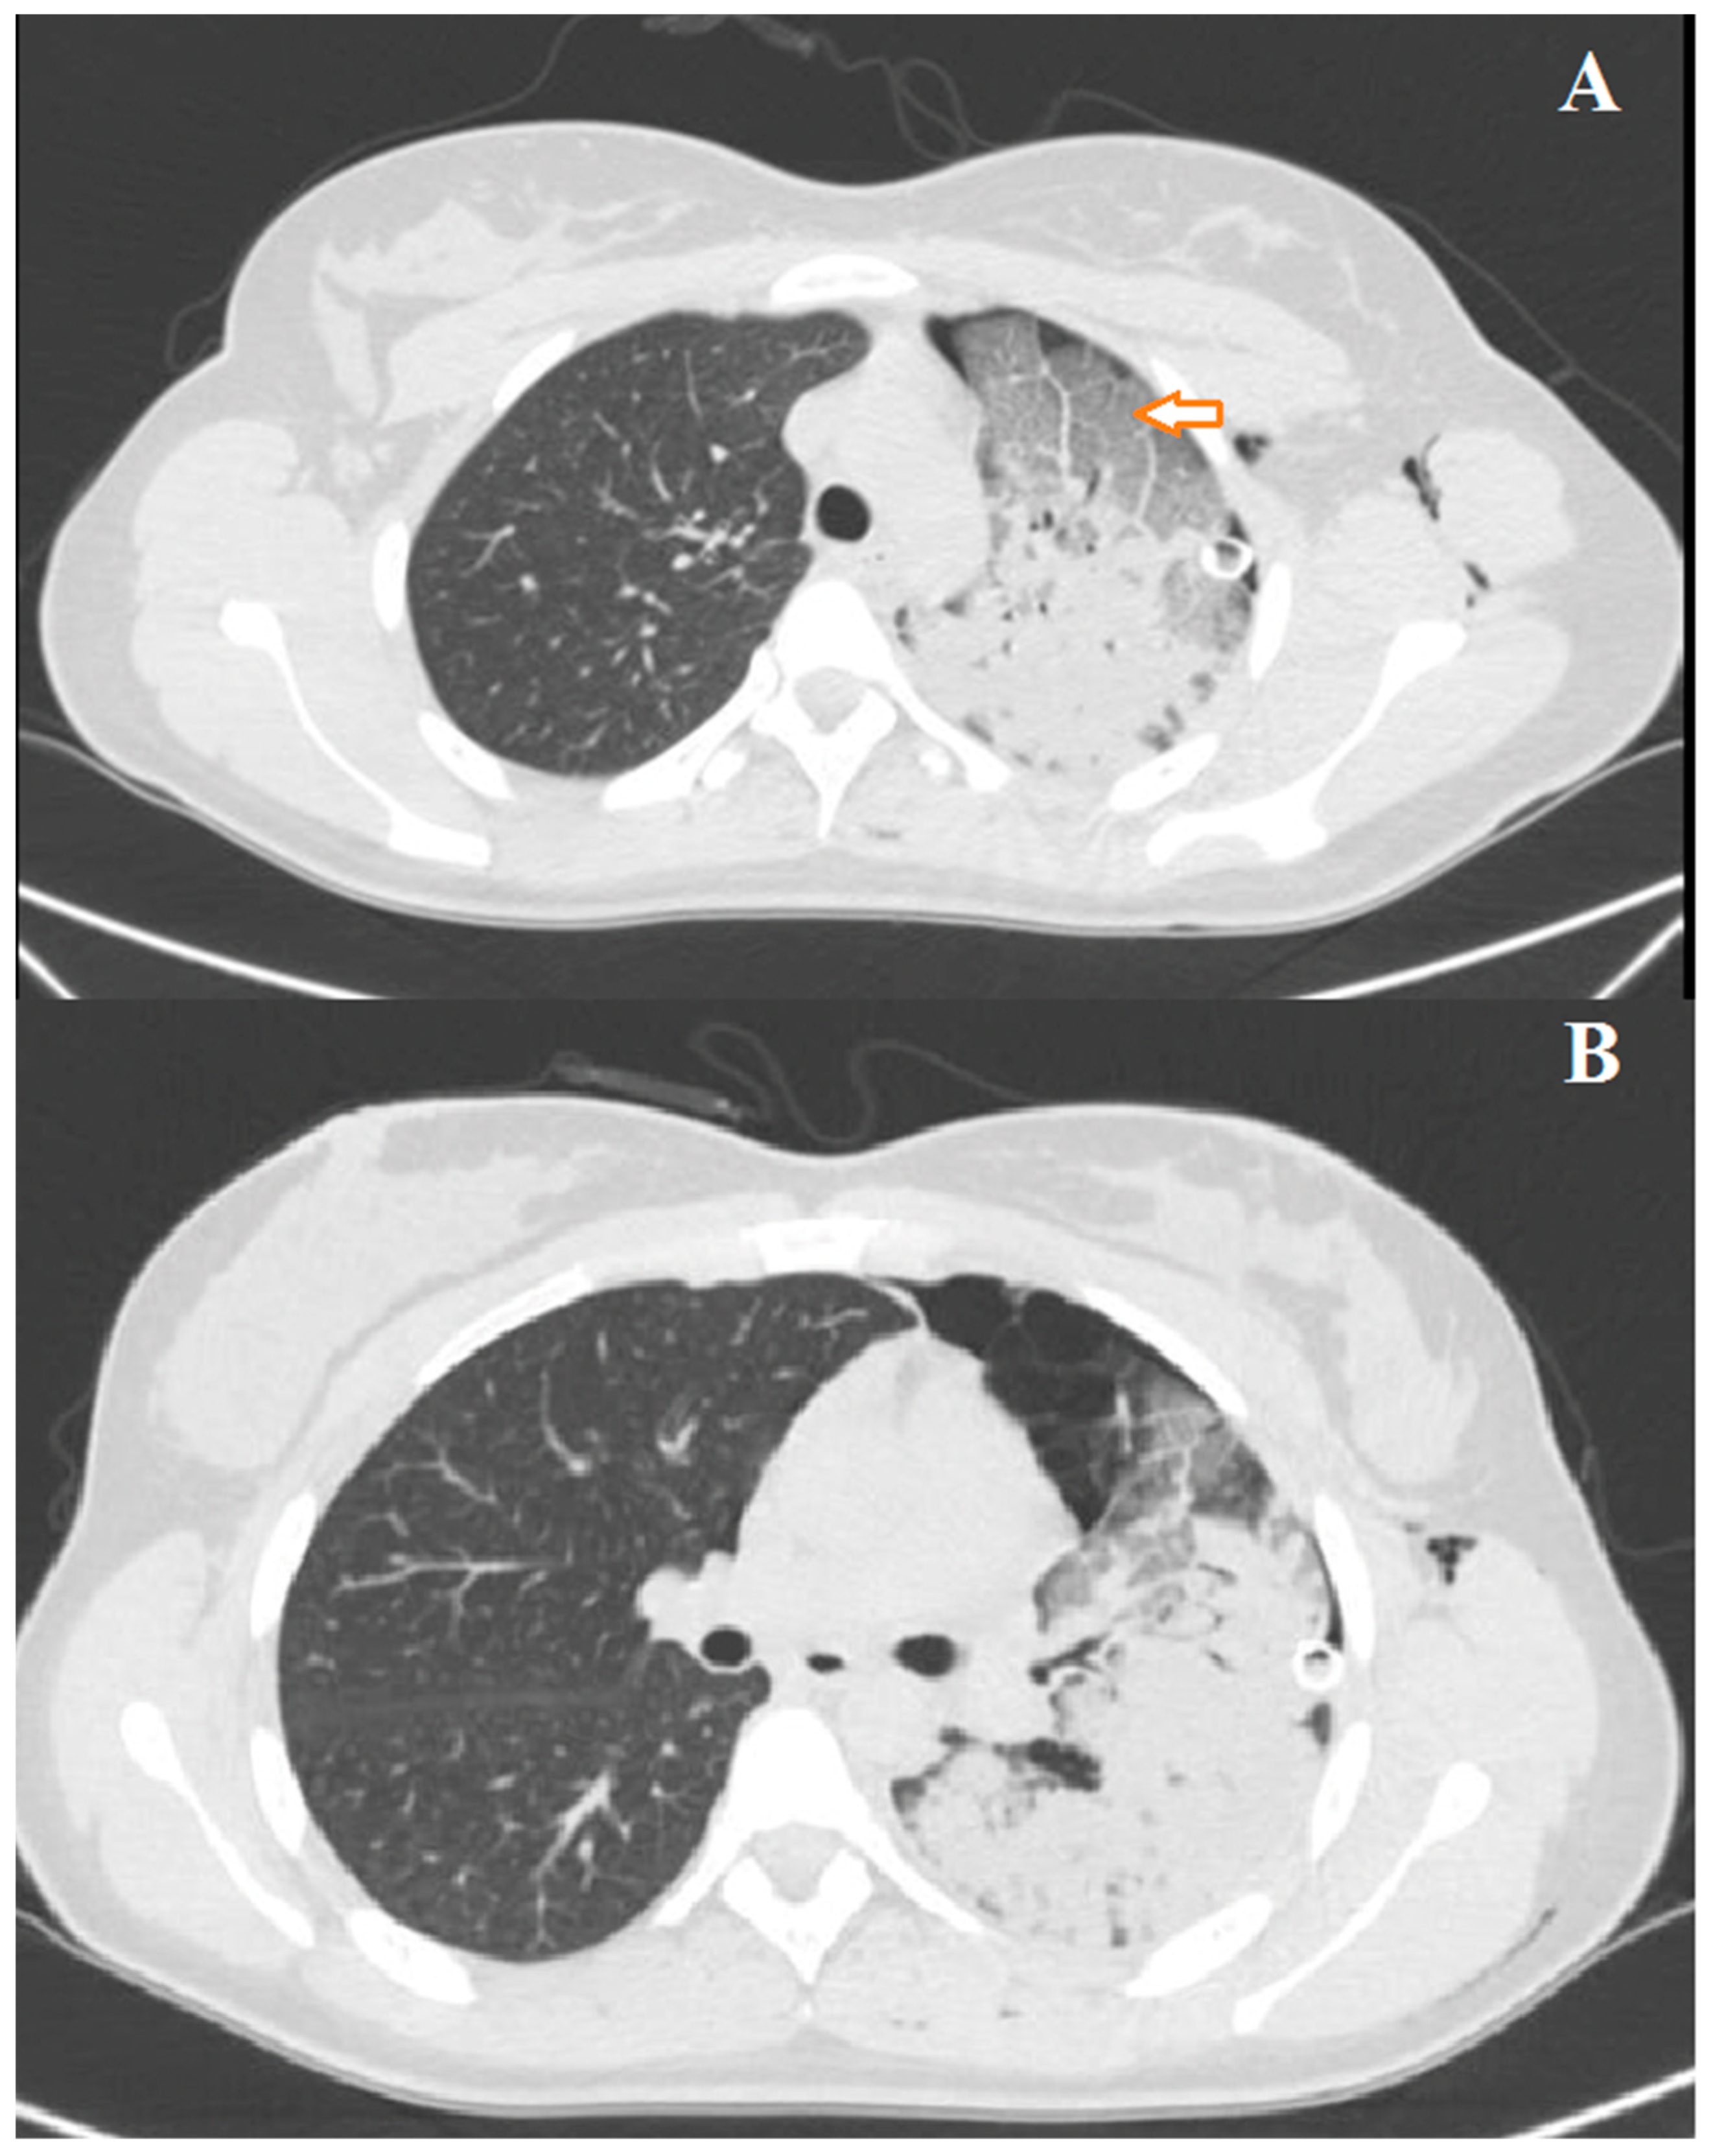

3.1. Case 1

3.2. Case 2